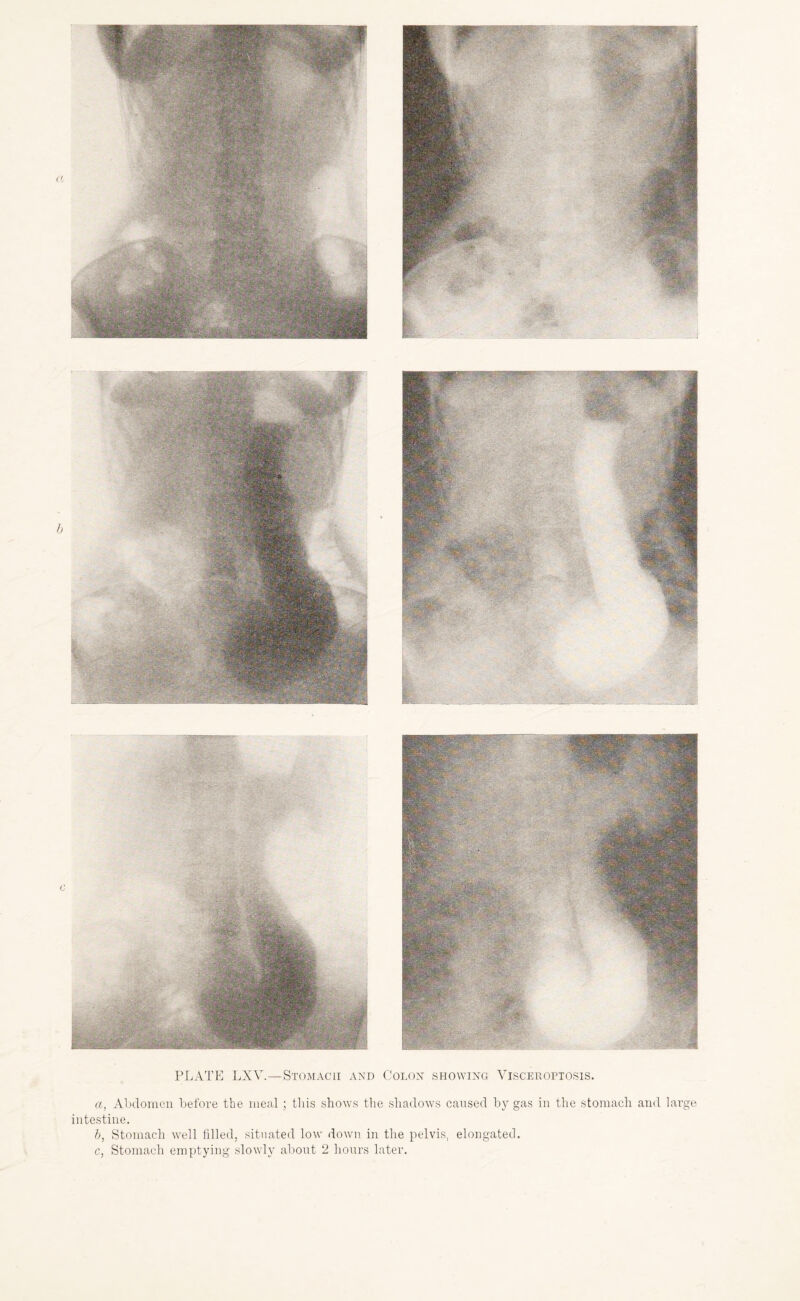

449/544 page 341